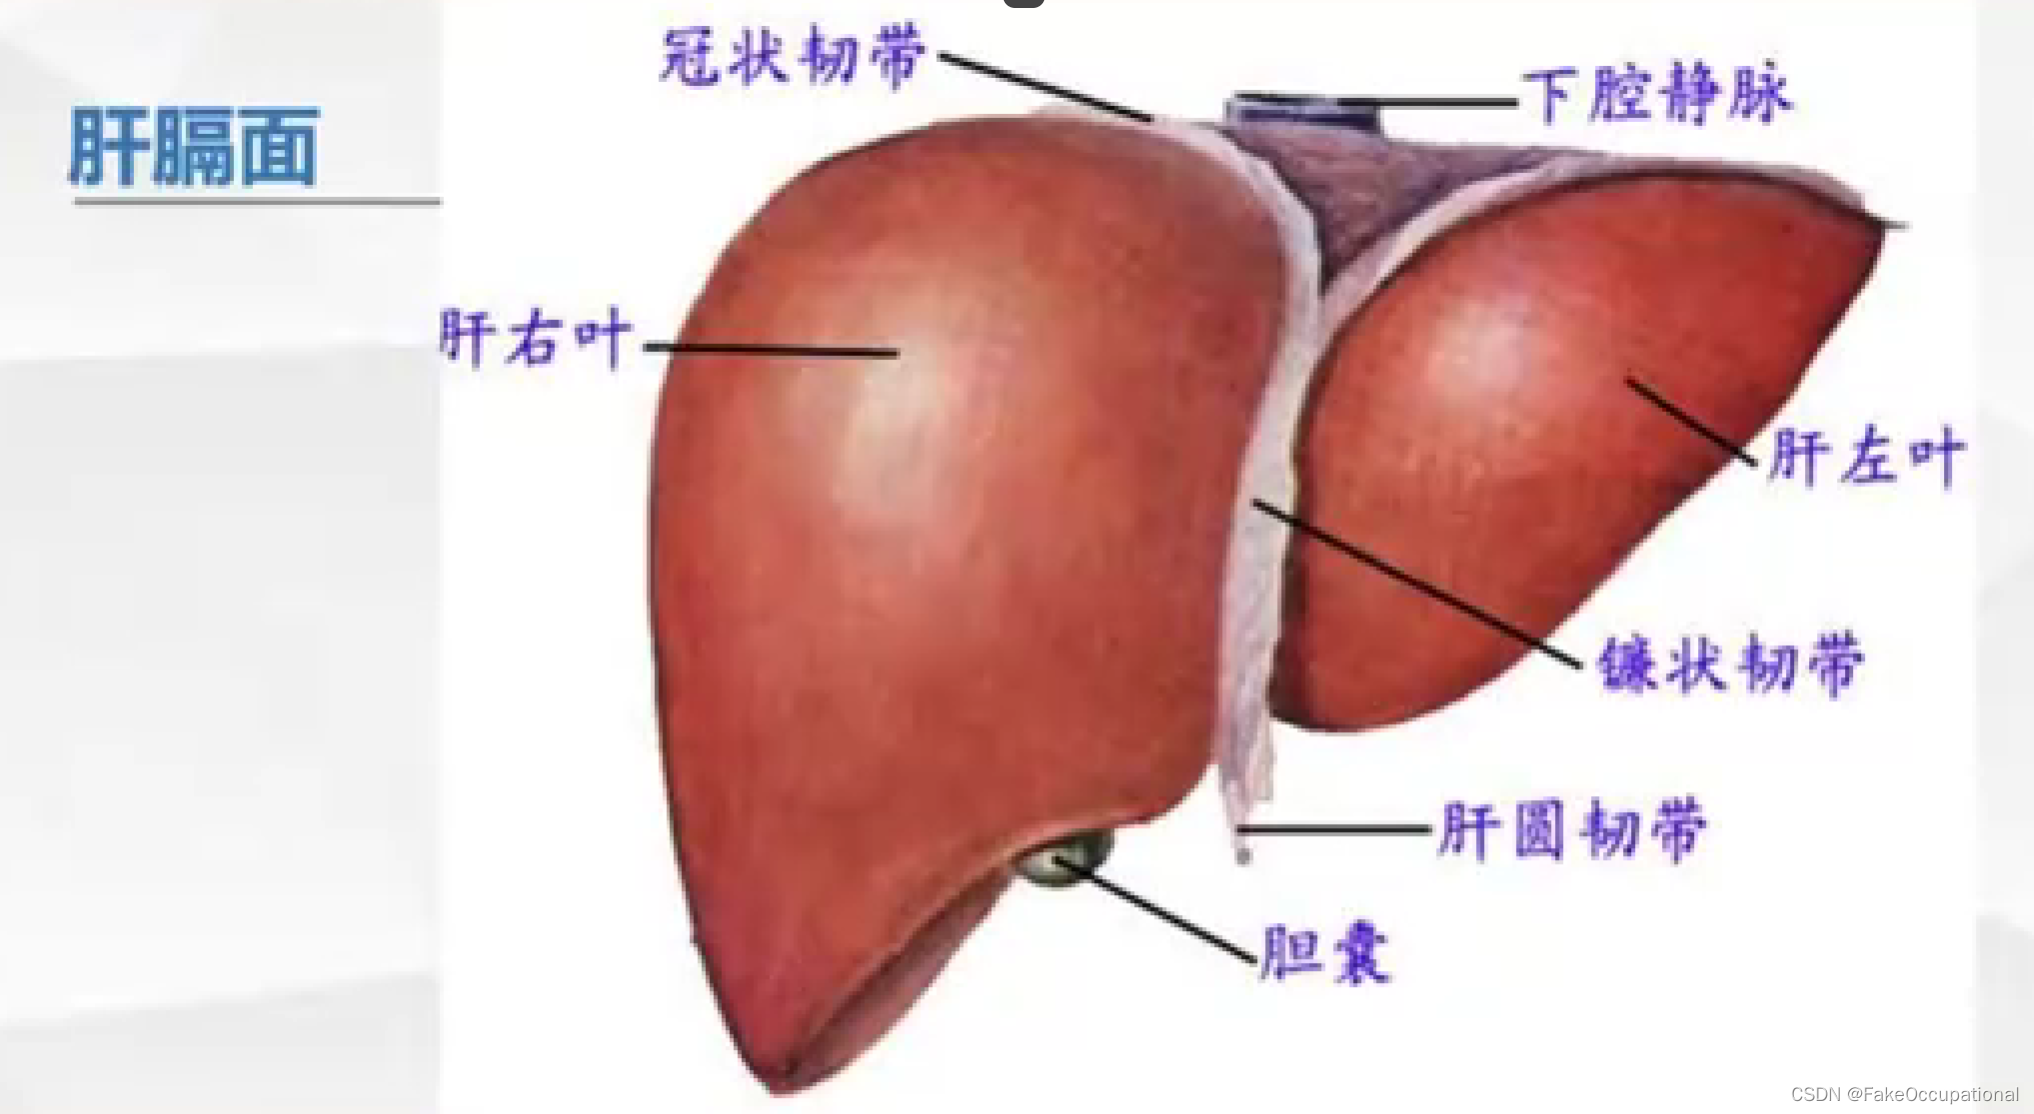

肝脏解剖概要